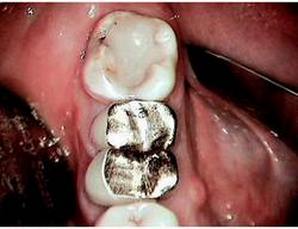

The education begins with showing the patient how the lack of remaining tooth structure makes any dental heroics unpredictable and economically unsound. We all need to respect the fact that even in a perfectly balanced occlusion, the prognosis of that “tired tooth” rebuilt with endodontic treatment, posts, cores, pins and crowns, in the absence of remaining natural tooth structure (ferrule), will in fact fail. It is just a matter of time. Once the educated patient accepts the futility of “the old standard of care,” they are now more open to understanding the “new standard of care”—dental implants.

As the primary dental care provider, the general dentist is perfectly positioned to not only make the diagnosis, but to educate and treat the patient to completion. Once the treatment has been accepted, the hopeless root (with no ferrule) is atraumatically extracted. If both the buccal and lingual walls remain intact, simple socket preservation techniques can be utilized so that in three to four months the general dentist now has “created” an optimal implant site. If pathology or less than traumatic extraction leaves you with a compromised buccal or lingual boney plate, then socket augmentation is performed, and an optimal implant site is available for implant placement in four to five months.